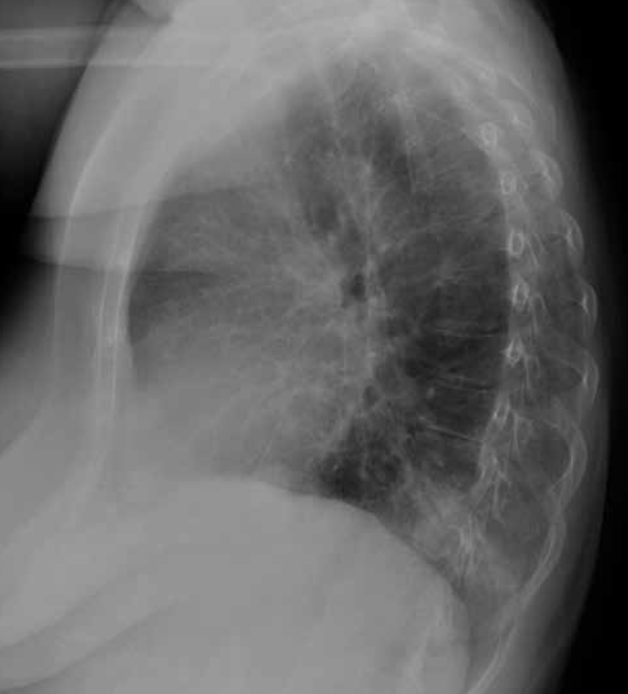

Signo de la silueta en placa de tórax PL.

Neumonía del lóbulo inferior izquierdo. La consolidación del lóbulo inferior izquierdo borra el contorno de la aorta descendente (infiltrado retrocardiaco).